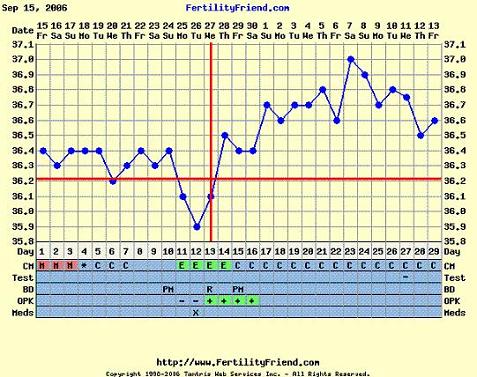

Holnap majd jövök az ideillő görbémmel